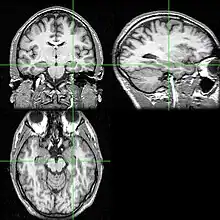

Las pruebas de neuroimagen pueden identificar la causa de las crisis y el foco de las crisis, es decir, el lugar del cerebro donde comienzan las crisis.[5] En la epilepsia recién diagnosticada, la resonancia magnética (RM) puede detectar lesiones cerebrales en hasta el 12-14% de las personas con epilepsia.[31] Sin embargo, en las personas con epilepsia crónica, la RM puede detectar lesiones cerebrales en el 80% de las personas con epilepsia.[31] La RM de 3-Tesla se recomienda para aquellos con evidencia de epilepsia focal, como la epilepsia del lóbulo temporal.[5] Las anomalías identificadas mediante RM incluyen esclerosis hipocampal, displasia cortical focal, otras malformaciones cerebrales corticales del desarrollo, tumores del desarrollo y de bajo grado, hemangioma cavernoso, lesión cerebral hipóxico-isquémica, lesión cerebral traumática y encefalitis.[5]